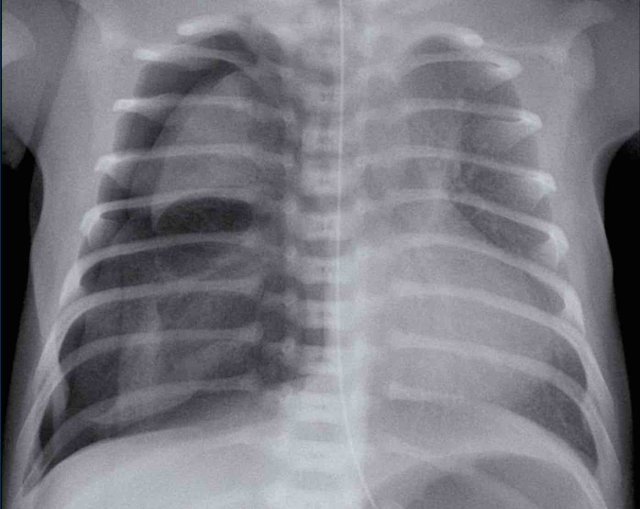

Image

One day old neonate, 27 weeks of gestational age.

Granular opacification of both lungs.

Vessels and cardiac silhouette are well depicted.

Conclusion: RDS grade 1.